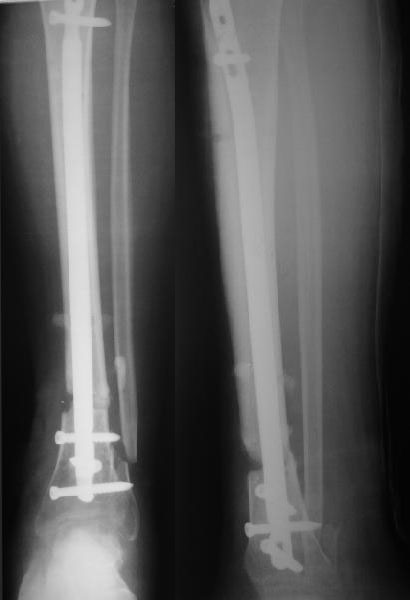

Здравствуйте коллега! Интересный случай! Буквально 3-4 месяца назад столкнулся с подобной ситуацией. Плюс у больного имелась нейропатия малоберцового нерва, стойкая эквинусная деформация стопы. Молодой человек лечился в другом лечебном учреждении. Первым этапом выполнено удаление стержня ChM, наложен аппарат внешней фиксации, в течении недели проводилось устранение имеющихся деформаций. Вторым этапом выполнен ЗИМО стержнем MetaDiaFix-T большего диаметра (картинки в приложении).

Если небольшой, то я бы убрал все винты, наложил дистрактор, гвоздь подтянул проксимальнее, не выводя окончательно из дистального отломка.

Длина и ось легко восстановятся. После чего гвоздь ввести снова и запереть.

Удаление, аппарат с дозированной коррецией и отсроченный реостеосинтез - это уж на крайний случай, если совсем тугоподвижность.

План, близкий к Вашему (реостеоситнкез после коррекции оси и длины) наиболее надежен. Минус - это вторая операция. Все остальные перечисленные варианты - в той или иной мере надежда на "авось".